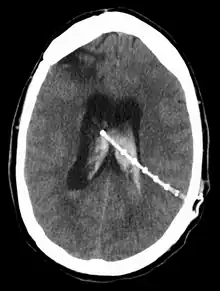

Intraventricular hemorrhage

An intraventricular hemorrhage can occur at any time during or after a shunt insertion or revision. Intraparenchymal hemorrhages that are multi-focal in nature have also been described in the pediatric population following ventriculoperitoneal shunting.[38] The hemorrhage can cause an impairment in shunt function which can lead to severe neurological deficiencies.[35] Studies have shown that intraventricular hemorrhage can occur in nearly 31% of shunt revisions.[39]